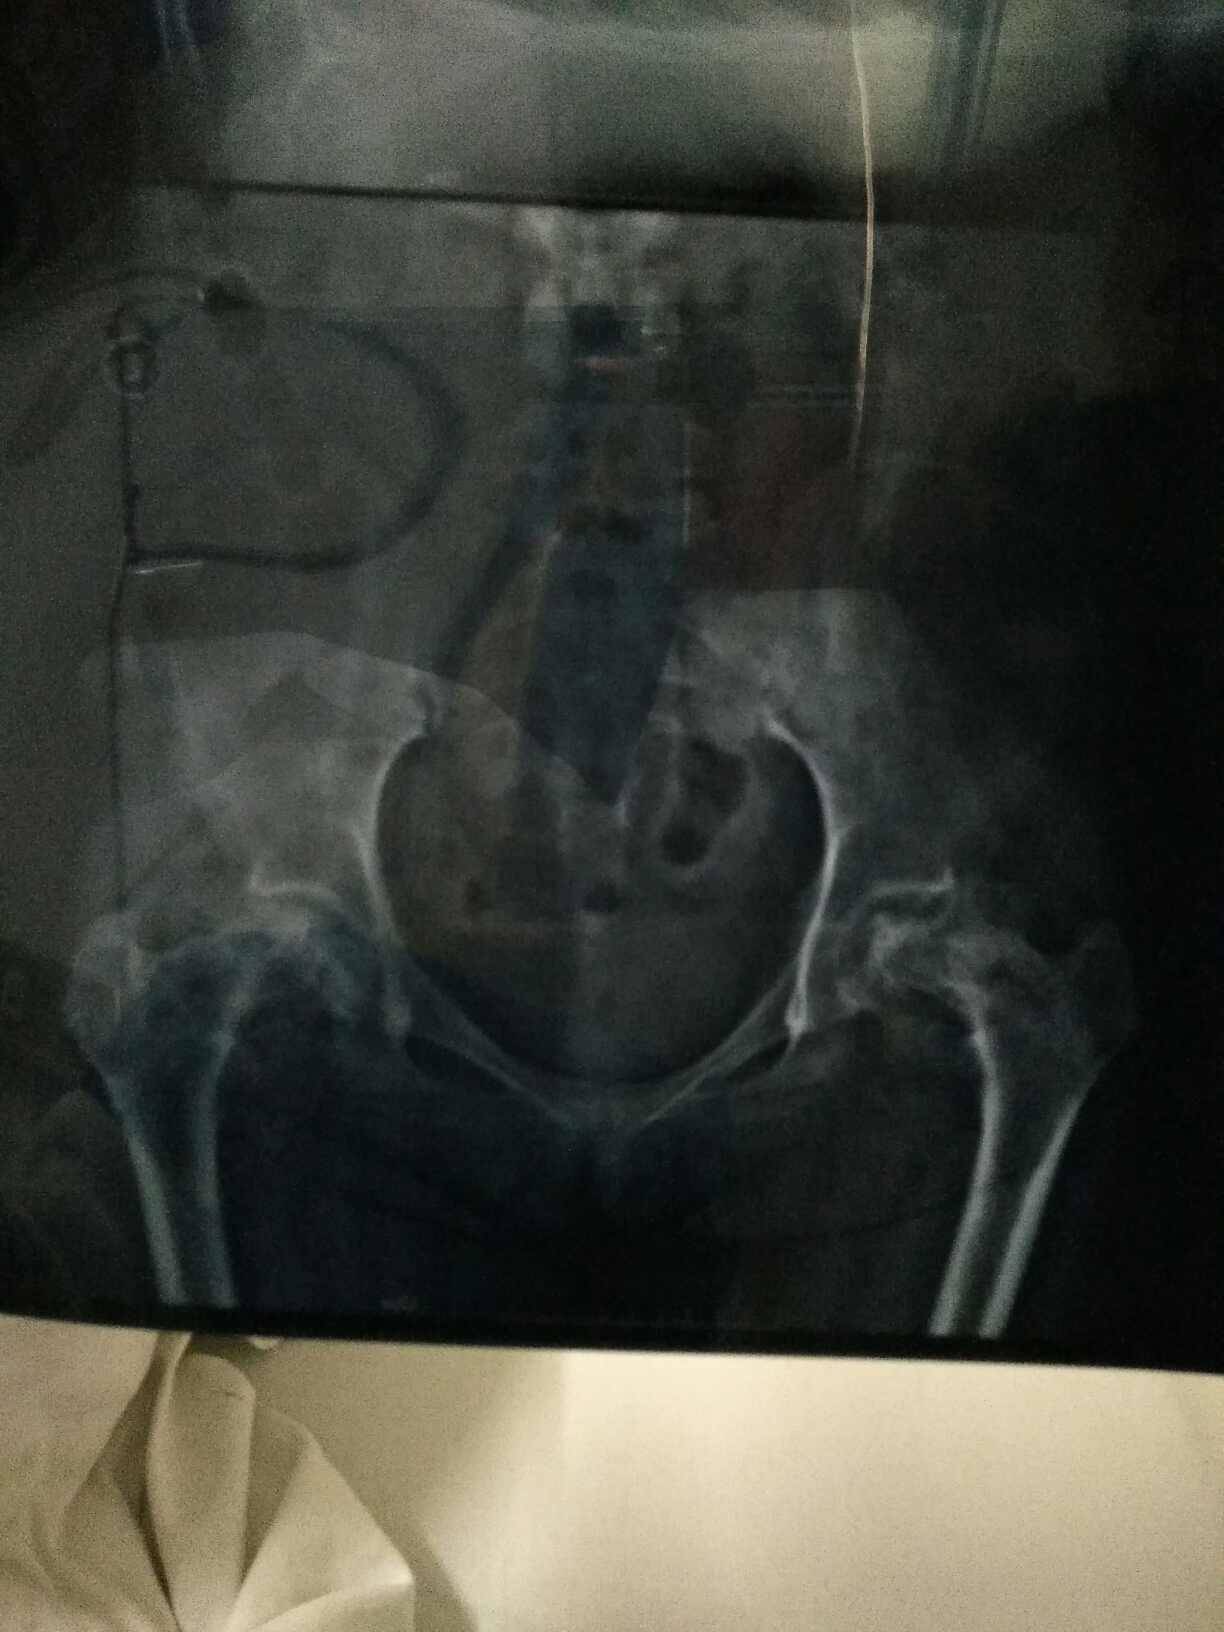

不太清楚照的,但是看的出来很严重了

因为膝盖也疼,活动弯曲还咔咔响,所以也拍了片子,万幸不是膝盖坏死。至于股骨头,已经很严重了,因为拖的太久,加上还减压过,所以在这里我劝如果有股坏的病友,千万不要去做减压和植骨,因为压根没有用,本身我们就停不了激素,所以做也是枉然,不严重的可以多活动,骑自行车,无负重锻炼,泡脚,也可以吃些活血的中药,但是要去正规的医院开,至于严重的还是手术吧,因为除了手术真没办法了